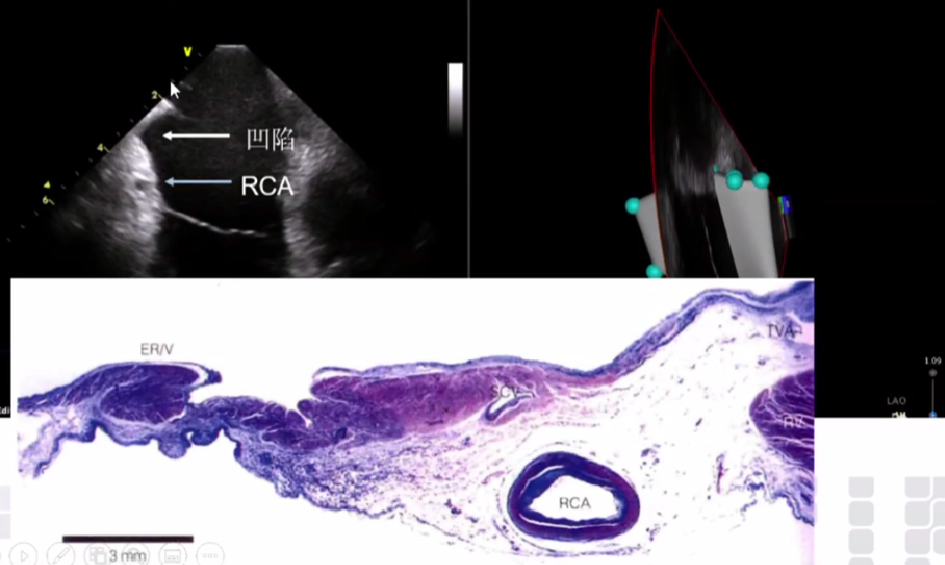

ICE-相对平坦的三尖瓣峡部

连接凹陷两端的肌束

超声观察到右冠状动脉

比较长的三尖瓣峡部